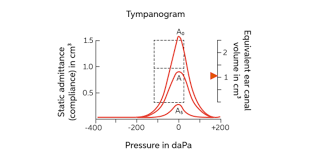

♦Tympanogram/Tympenometry ( ટીમપેનોગ્રામ)

- આ ટેસ્ટમાં એક નાના પ્રોબને Ear ની અંદર place કરવામાં આવે છે. અને air પ્રેશર અપ્લાય કરવામાં આવે છે.આ ટેસ્ટ એ ઓડિયોલોજિસ્ટ દ્વારા eardrum અને મિડલ ઈયરના સ્ટ્રક્ચર નું વર્કિંગ કન્ડિશન કેવી છે તે ચેક કરવા માટે કરવામાં આવે છે. Ear canal volume એ Ear ડ્રમનું પરફોરેશન છે કે નહીં તે દર્શાવે છે.મિડલ ઈયર નું પ્રેશર એ દર્શાવે છે કે ફ્લુઈડ એ મિડલ ઈયર ની સ્પેસમાં છે કે નહીં.આનુ મેજરમેન્ટ દર્શાવે છે કે Ear drum અને ત્રણ મીડલ ear ના બોન્સ એ બરોબર વર્ક કરે છે કે નહીં તે જોવા માટે કરવામાં આવે છે.